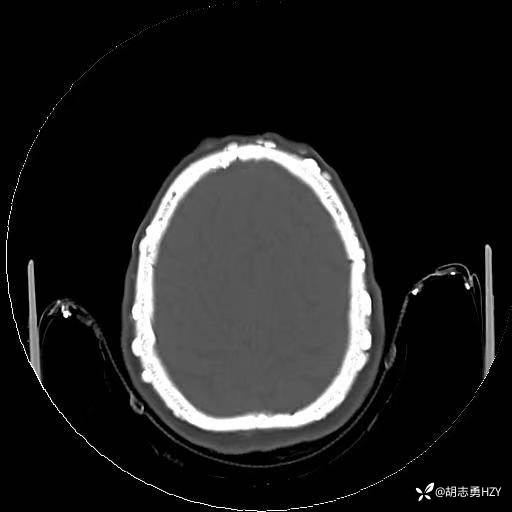

女性,45岁,家族性腺瘤性息肉病,额部顶部多发无痛性硬质包块